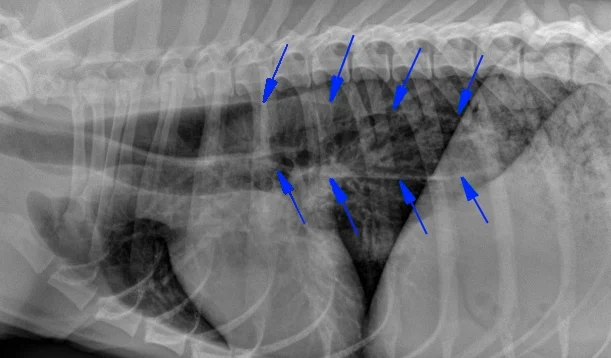

The condition affects your canines muscles and shortens their life expectancy in some severe cases. Myasthenia Gravis in dogs is a neuromuscular disease caused by a malfunction in the signal transmission between the nerves and muscles resulting in fatigue and muscle weakness. Years ago early death occurred in over a.

Megaesophagus Mar Vista Animal Medical Center

Megaesophagus Vca Animal Hospital